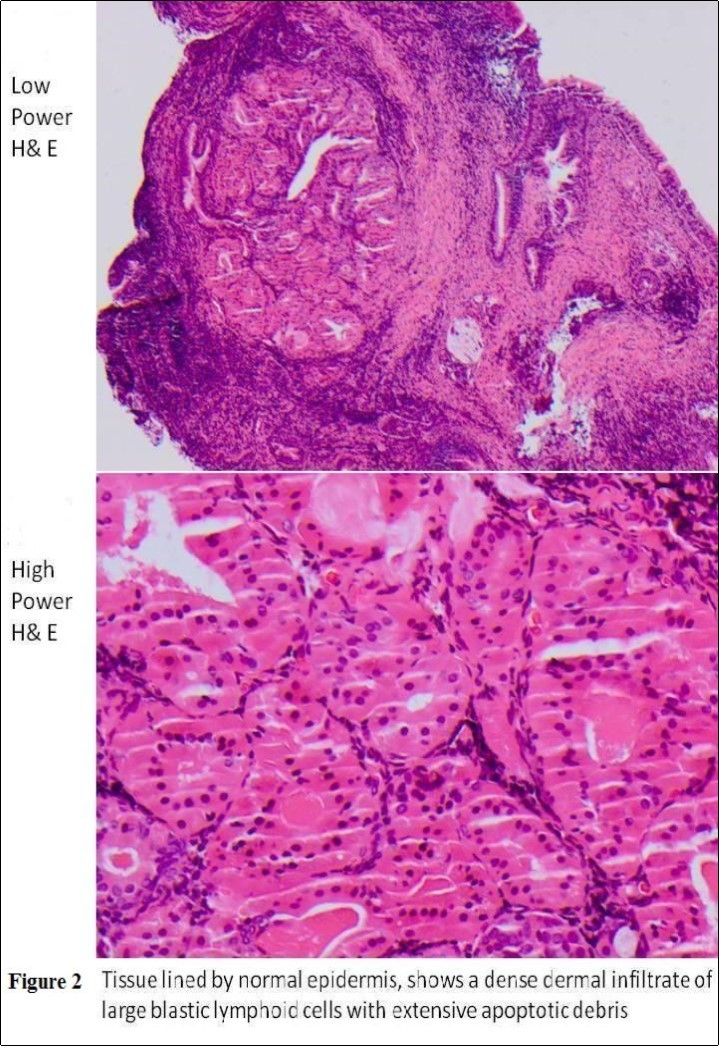

Six Biopsies (3 mm) were taken from the mass of right ear under local anaesthesia. The histology was keratinised stratified squamous epithelium with underlying variable infiltrate of large atypical lymphoid cells suggestive of high grade non Hodgkin’s lymphoma (Figure 2).

Figure 2.Low/High Power H & E: Dermal infiltrate of large blastic lymphoid cells

The immunohistochemical confirmed infiltrating lymphoid blasts CD45 positive, CD30 negative, cytokeratin negative and CD5 negative, CD20+ B lymphoid blasts with few scattered CD3+ T lymphocytes in the background. The B lymphocytes are CD79+a, CD5 weak +, CD10-, CD21-, CD23-, Bcl-2+, Bcl-6+, CD43-, MUM1+. Ki-67 staining shows a high proliferation index approaching 60%.